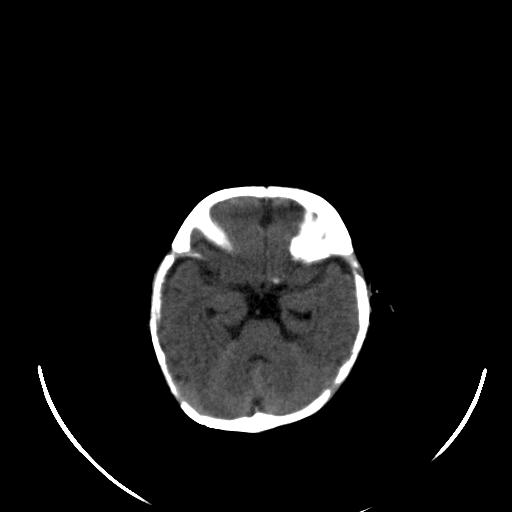

患儿 女性 1个月  今天发现阵发性抽搐  双眼上翻、凝视,嘴唇及面色青紫

双侧颞枕叶片状低密度影,考虑新生儿却血缺氧性脑病可能

左侧额叶见班片样低密度灶,症状像癫痫,可能与之有关。

新生儿却血缺氧性脑病不排除!

左侧额叶见班片样低密度灶,建议mr

考虑hie。

考虑新生儿hie。